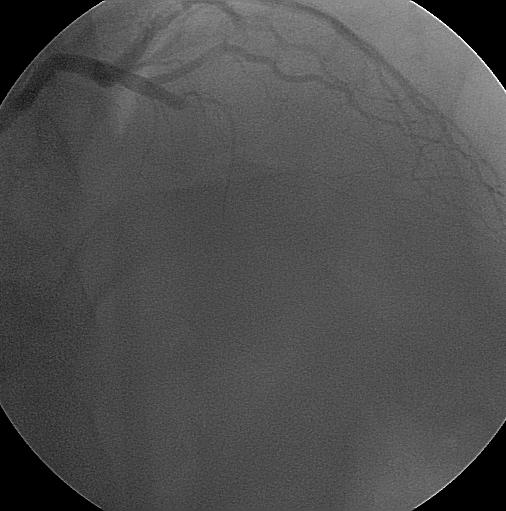

Koroner stent uygulamasında ise darlık veya tıkanıklık bölgesine bir balonun üzerinde sıkıştırılmış tel kafes bulunur, bu üzerinde tel kafes olan balon darlık bölgesinde şişirilince üzerindeki tel kafes genşileyerek damar duvarına gömülür ve darlığı dışarı doğru iter, sonra balon indirilip geri çekilir, stent o bölgede kalır, yaklaşık 4-6 hafta sonra stentin üzeri damar katmanı ile örtülür, yani damar KORONER STENT

içinden bakılınca stent gözle görülmez. Stent uygulama işleminden sonra aynı bölgede tekrar daralma olması riski yaklaşık %30-40'dır, ama yine şeker hastalarında, ince damar çapı olanlarda, darlık bölgesi uzun olanlarda bu oran daha da yüksek olabilir.

İlaçlı stentlerde ise stent üzerinden yavaşça salınan bir ilaç damarın tekrar daralma riskini azaltmaktadır, bu stentlerin tekrar daralma riski ise %5-10 civarındadır. |